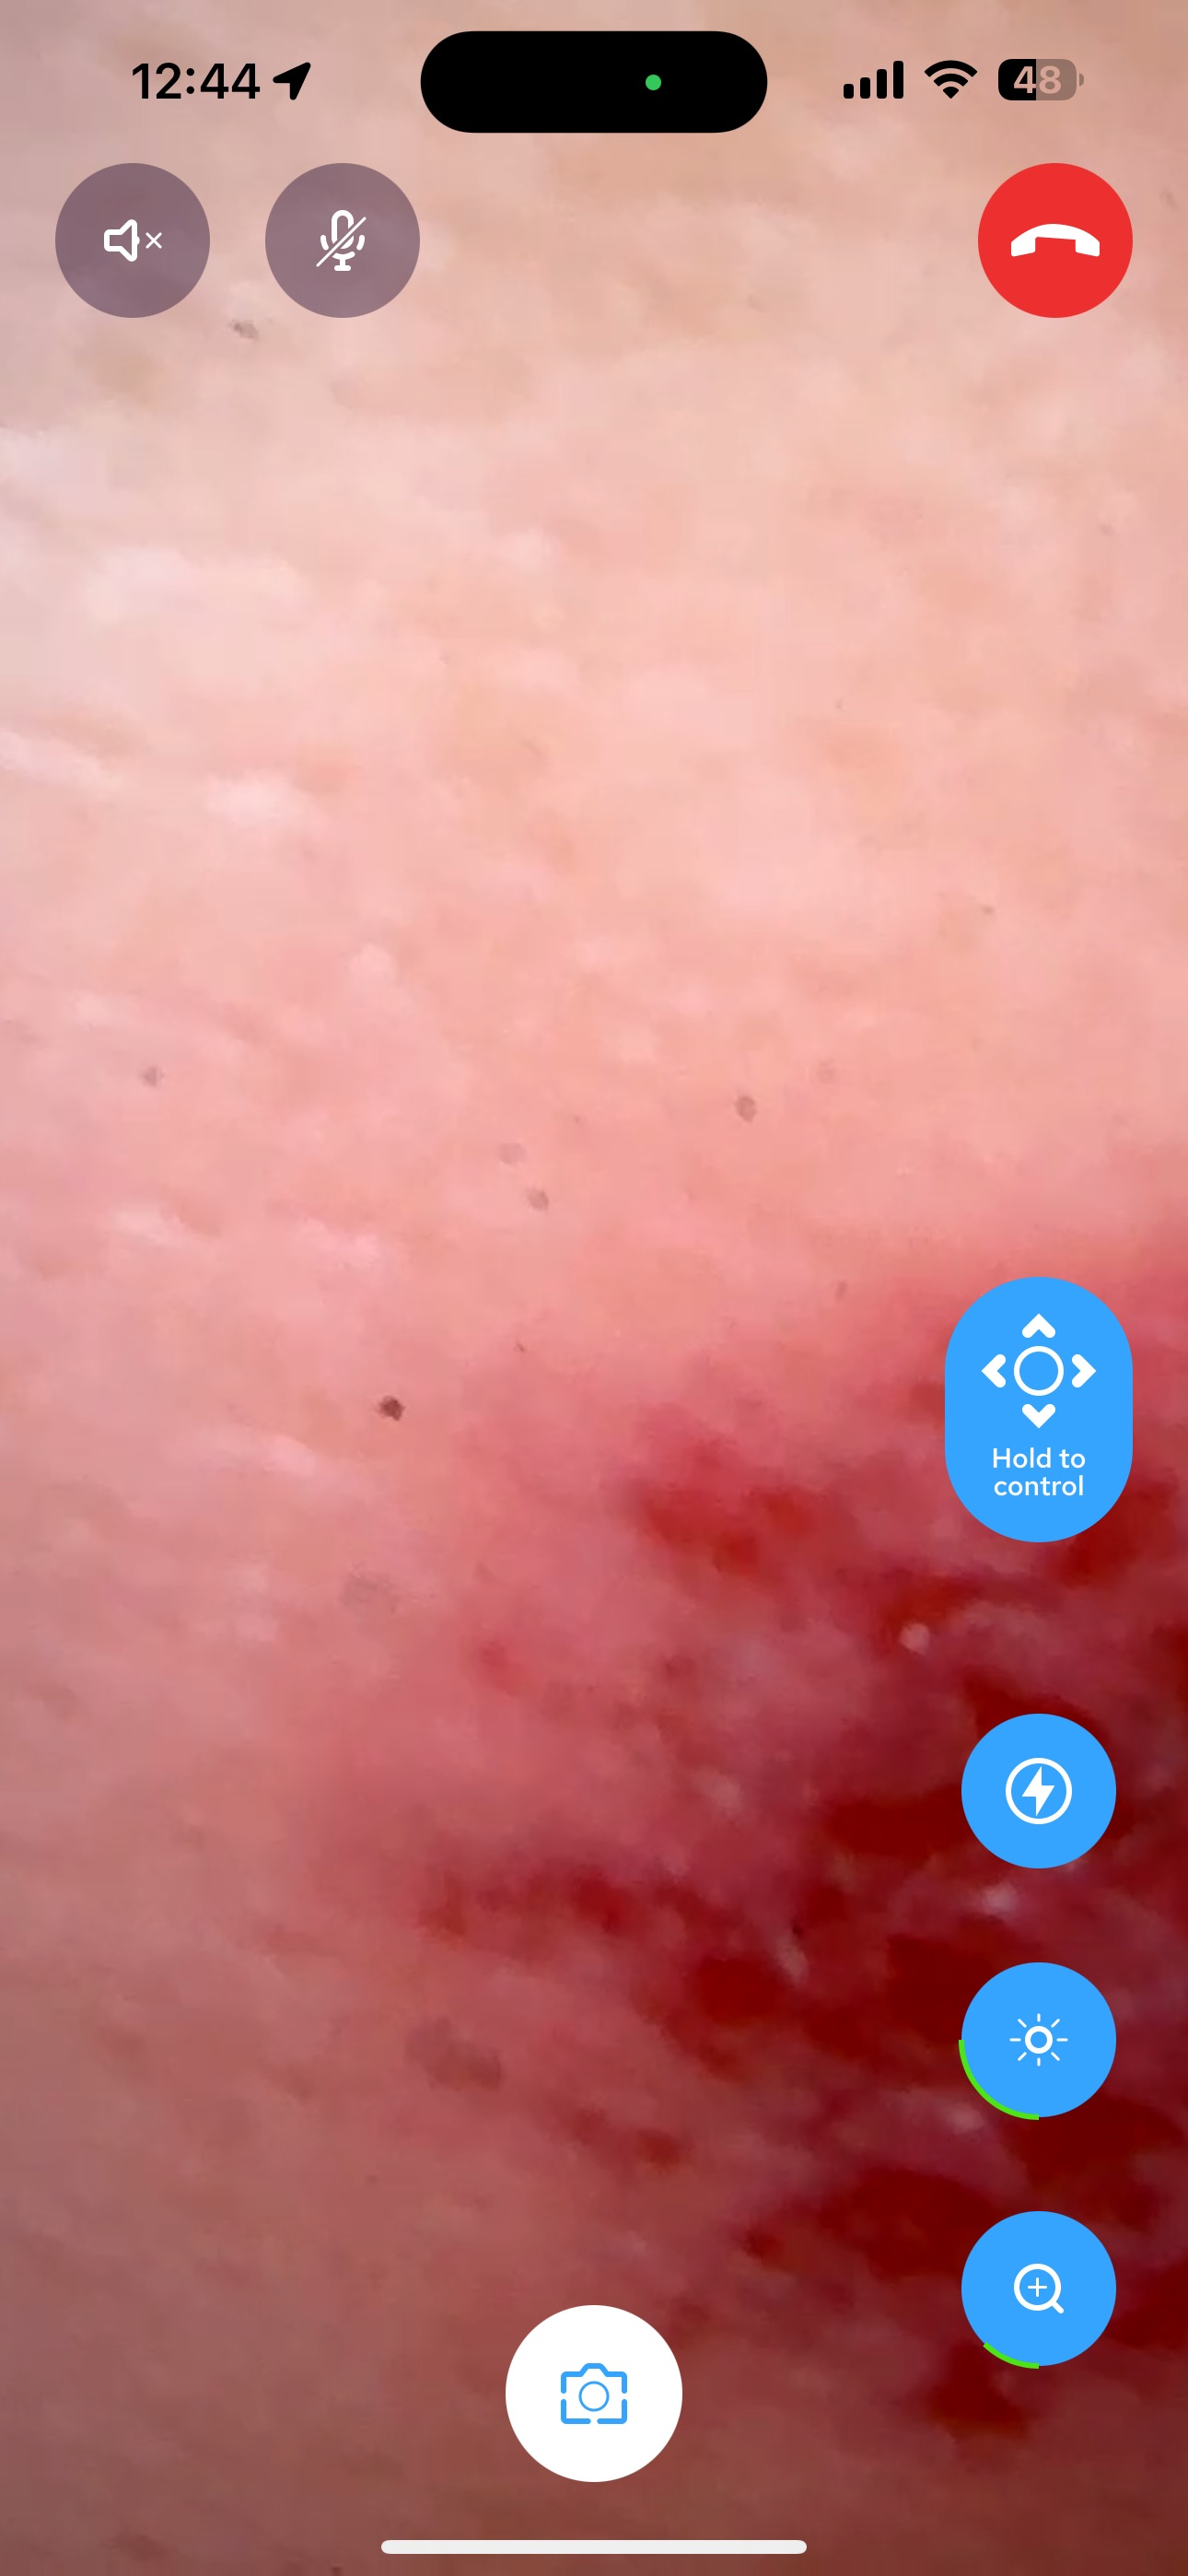

SeaGreen is a secure, open, free to use platform for healthcare professional to connect and collaborate. SeaGreen streamline consultation and collaboration such as AI powered capture mode that anonymize and a software virtual operating room.